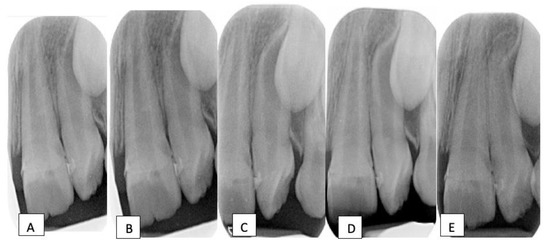

2.1. Clinical Examination and Diagnosis

2.2. Treatment Plan and Progress